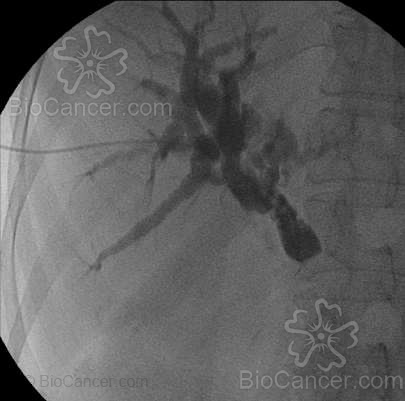

Figura 2.- Opacificación de la vía biliar mediante punción transparieto-

hepática que evidéncia obstrucción en colédoco pancreaticoy consiguiente

dilatación de la vía biliar proximal a la obstrucción.

La punción de la vía biliar dilatada, se realiza a través del 10º espacio intercostal con una aguja de muy pequeño calibre, que se introduce a nivel de la línea medio-axilar tras la aplicación de anestesia local y en ocasiones acompañada de sedación. Tras varios pasos intermedios, se ubica un catéter en la porción proximal de la vía biliar con el que ya se puede retirar la bilis al exterior (drenaje biliar externo) (Fig.2). Si pasamos con un catéter apropiado, podremos ubicar un catéter con muchos orificios en la porción proximal y distal de la obstrucción (drenaje biliar interno), de esta forma la bilis ya no será retirada al exterior, sino que pasará al tubo digestivo a través de los orificios del catéter. En ocasiones, tras efectuar el estudio de extensión del tumor, se podrá indicar la liberación de una prótesis en la zona ocluida, con lo cual el paciente no dependerá de un catéter para el drenaje de su bilis (Fig.3). La limitación de las prótesis en la vía biliar está, igual que pasaba con las esofágicas en su corto período de permeabilidad, hecho este que las limita para usar solo en pacientes con expectativa de vida corta.